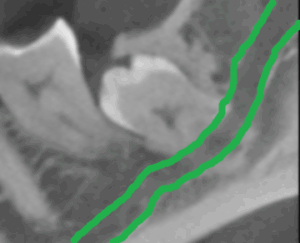

Auf dem ersten Röntgenbild ist ein Weisheitszahn dargestellt, der noch unter der Schleimhaut liegt. Unklar ist der Verlauf des Nervs, der unter anderem einen Teil der Unterlippe mit Gefühl versorgt. Auf der nächsten Abbildung ist der Nerv zum besseren Verständnis grün dargestellt. Die gängige, zweidimensionale Röntgentechnik kann Fragestellungen der exakten Zahnlage sowie des Nervenverlaufs nicht klären. Unsere Praxis verfügt über die modernste strahlenarme 3D-Röntgentechnik (DVT), welche es uns ermöglicht, relevante anatomische Strukturen dreidimensional zu beurteilen.

Auf der ersten Abbildung ist der gleiche Weisheitszahn mit modernster 3D-Röntgentechnik im Querschnitt dargestellt. Deutlich ist zu erkennen, dass in dieser Situation die Zahnwurzel den Nerv komplett umgreift. Zum besseren Verständnis ist der Nerv auf der zweiten Abbildung grün dargestellt.